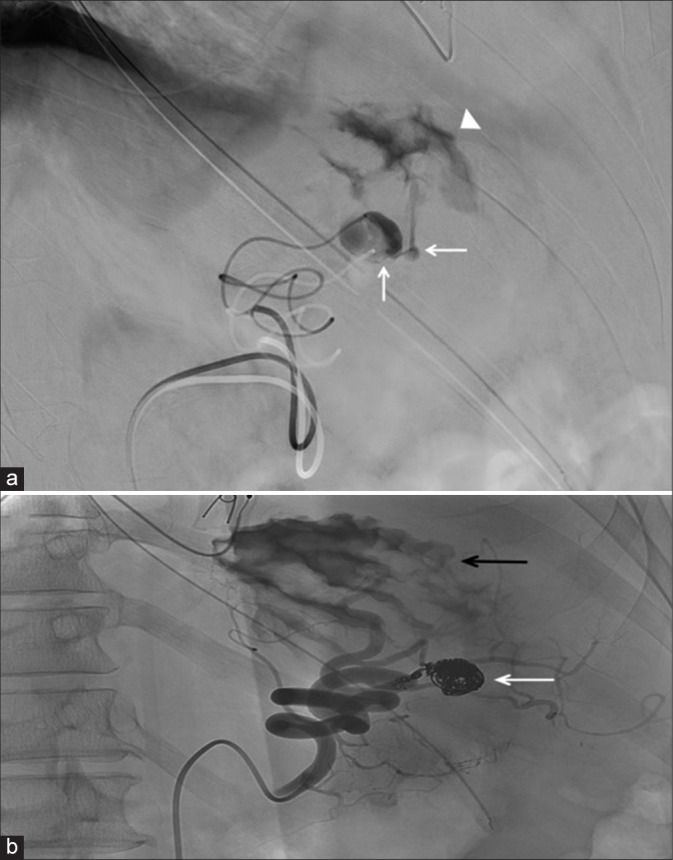

绝大多数因危重消化道出血(GIB)而入住重症监护室(ICU)的患者都有可预测的病因。一旦出血部位被定位在上消化道或下消化道,通常遇到的病因就非常有限。在极少数情况下,需要重症监护病房治疗的 GIB 的病因并非标准考虑因素之一,这可能会导致诊断和治疗延误。在很短的时间内,我们医院的内科重症监护室就收治了三名患者,每名患者的 GIB 病因都出乎意料。这三个病例都产生了各种具有启发性的图像,本系列文章将用这些图像来说明这些病症以及放射科在其评估和管理中的作用。

The great majority of patients admitted to the intensive care unit (ICU) for critical gastrointestinal bleeding (GIB) will have a predictable etiology. Once the site is localized to the upper versus the lower gastrointestinal tract, the number of typically encountered etiological possibilities is quite limited. On rare occasions, the cause of GIB requiring ICU care is not one of the standard considerations, potentially leading to diagnostic and therapeutic delays. Within a short time period, three patients were admitted to our institution's medical ICU each with a different unexpected cause of GIB. All three cases generated a variety of instructive images, which are used in the present series to illustrate these conditions and the role of radiology in their evaluation and management.